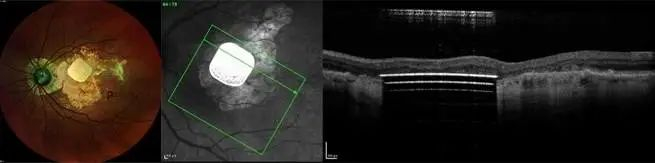

早在 2018 年,它们的小型无线光伏视网膜下植入物 PRIMA 就被 FDA 批准开始临床研究。

这是一种由无线视网膜下植入物和增强现实眼镜组合而成的「仿生眼」。

而且,它比 Argus II 更小、更简单、更便宜,还无需动脑部手术。

2019 年,法国 5 名患有晚期干性 AMD 的患者植入 PRIMA 的 12 个月数据表明,所有人的视网膜中央都成功引发了光感。

12 个月后,大多数患者可以识别字母,还有一定的字母序列,且没有与设备相关的不良反应,现在,他们正在欧洲和美国进行可行性试验。